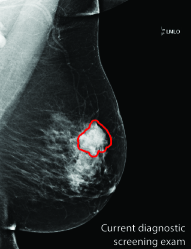

Masking refers to the phenomenon in which a tumor is hidden by the surrounding breast tissue, causing the cancer to be difficult or even impossible to discern with regular mammography, as seen in Figure 2. Masking can also result in large invasive cancers111We define large invasive cancers as those confirmed to have spread and be 2cm at time of diagnosis. – a small cancer may be difficult to discern in certain images, allowing it to grow to a more lethal size. Masking is correlated with breast density, as it has been shown that cancer in dense breasts is more likely to be missed during screening [5, 6, 7]. Density can be subjectively assessed by radiologists via the BI-RADS density standard (ACR) [8, 9], or measured by automated tools such as Libra [10]. These density measurements, however, do not perfectly correlate with masking potential. Radiologists consider the distribution and pattern of tissue when assessing masking potential, and have called for automated methods to assess the masking effect [11]. Until now, the question of exactly how masking potential should be quantified remains an open one, although some subjective notion has been added to certain categories of the most recent edition of BI-RADS density [12].

| Large invasive cancer | Same cancer, likely masked | Tumor size & frequency | |

|---|---|---|---|

![]() |